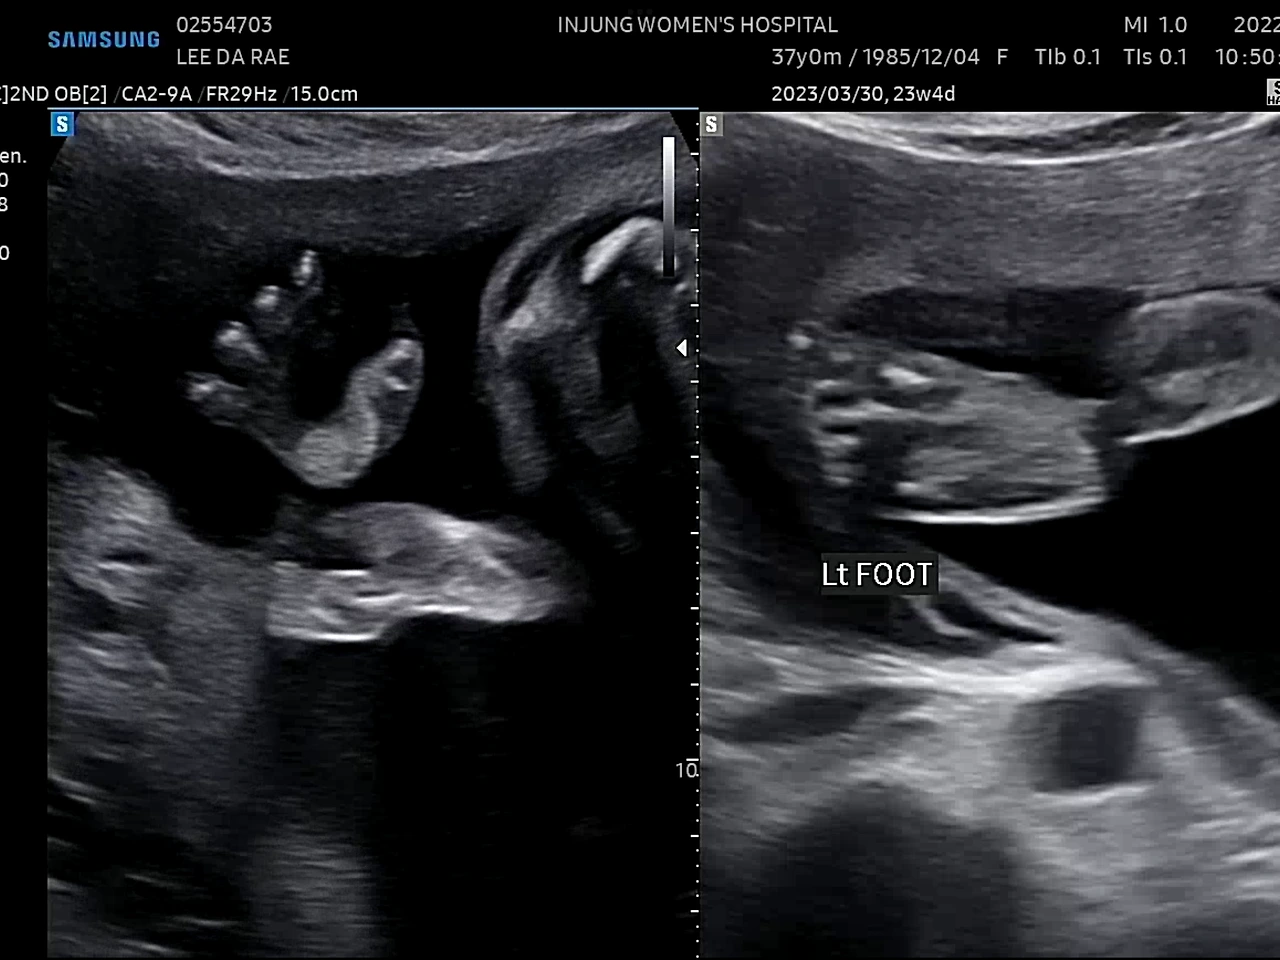

귀여운 손발

23주에 정밀초음파 검사를 받았다. 1차 기형아 검사에서 고위험군으로 나온 후로 모든 검사가 겁이 난다.(니프티검사에서 정상판정) 초음파 선생님(?)이 포도의 심장을 천천히 보시는데 한동안 아무 말씀도 없으시길래 너무 긴장이 됐다. 다행히 포도는 건강했다. 선생님이 아이가 쉬지 않고 움직인다고 하셨다. 아인이 때도 아이가 활발하다는 얘길 들었는데ㅋㅋ 남매라 그런가 비슷하네. 얼른 만나고 싶다 포도야!